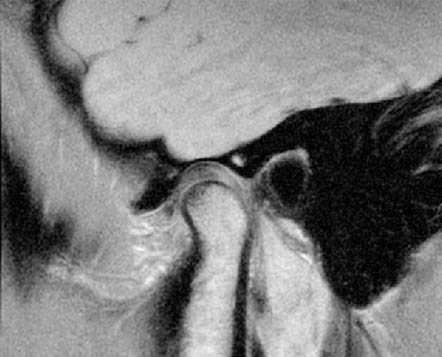

Косо-сагиттальная проекция с закрытым ртом. Нормальный ВНЧС.

Суставной диск не дислоцирован, задняя его часть находится на 12 часах циферблата мыщелка.

Нормальная мобильность диска

Позиция с открытым ртом. Мыщелок сместился вентрально, на уровень суставной ямки. При этом суставной диск сохранил нормальное положение интерпозиции, не давая костным структурам напрямую контактировать друг с другом.